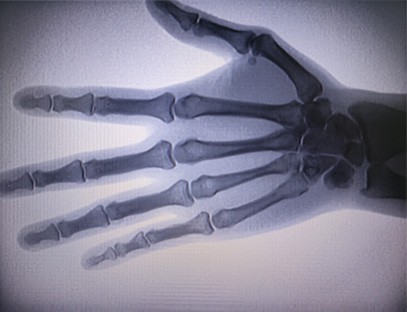

Portativ rentgen apparatiradiatsiya ta'sirini kamaytirgan holda yuqori sifatli tasvirlarni olish mumkin bo'lgan past nurlanish dozasi, juda xavfsiz portativ asbobdir. U katta kasalxona jihozlarining kamchiliklarini qoplaydi va istalgan vaqtda ko'chirish va olib yurish mumkin. Ayniqsa, byudjeti etarli bo'lmagan va tasvirlar uchun past talablarga ega bo'lgan birliklar va shaxslar uchun javob beradi. Bizning yangi avlod rentgen apparatimiz 10 dyuymli yuqori aniqlikdagi katta ekran bilan jihozlangan bo'lib, u kattaroq ko'rish burchagi diapazoniga ega va butun kaftni, jumladan, sinish, dislokatsiya, artrit va suyak o'smalarini to'liq ko'ra oladi. Ortopedik plyonkalarni chop etish uchun kino printeriga ulanishi mumkin, shuningdek, sanoat ishlab chiqarish va sinov uchun ham foydalanish mumkin. Qorong'i xonaga, to'g'ridan-to'g'ri istiqbolga, real vaqtda kuzatishga hojat yo'q. Ushbu mashinada yuqori aniqlikdagi tasvirlash tizimi mavjud bo'lib, u har qanday suyak strukturasining tasvirlarini juda aniq suratga olishi mumkin. Tibbiy, uy hayvonlari, sanoat, elektron mahsulotlar ishlab chiqaruvchilari, inspeksiya va texnik xizmat ko'rsatish bo'limlari va tadqiqot laboratoriyalari uchun eng yaxshi rentgen tekshiruvi uskunalari va echimlarini taqdim etish.

Ixtisosligi:Ortopediya klinikalari ehtiyojlari uchun mo'ljallangan, ayniqsa mos keladiRentgen tasviriqo'llar, bilaklar, tirsaklar, yelkalar, tizzalar, to'piqlar va boshqalar kabi a'zolarning.